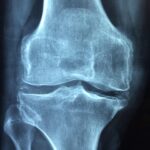

This in-depth joint pain workshop led by Vas Avramidis presents a holistic, root-cause approach to arthritis and chronic joint pain, combining herbal medicine, nutrition, and lifestyle strategies into a cohesive system for long-term healing.

But emerging research and traditional systems of medicine point to something deeper: Arthritis is often a systemic inflammatory condition, closely tied to metabolic health, gut integrity, and chronic lifestyle patterns.

- The difference between osteoarthritis and rheumatoid arthritis

- Why inflammation, not aging, is the primary driver

- The metabolic connection behind joint degeneration